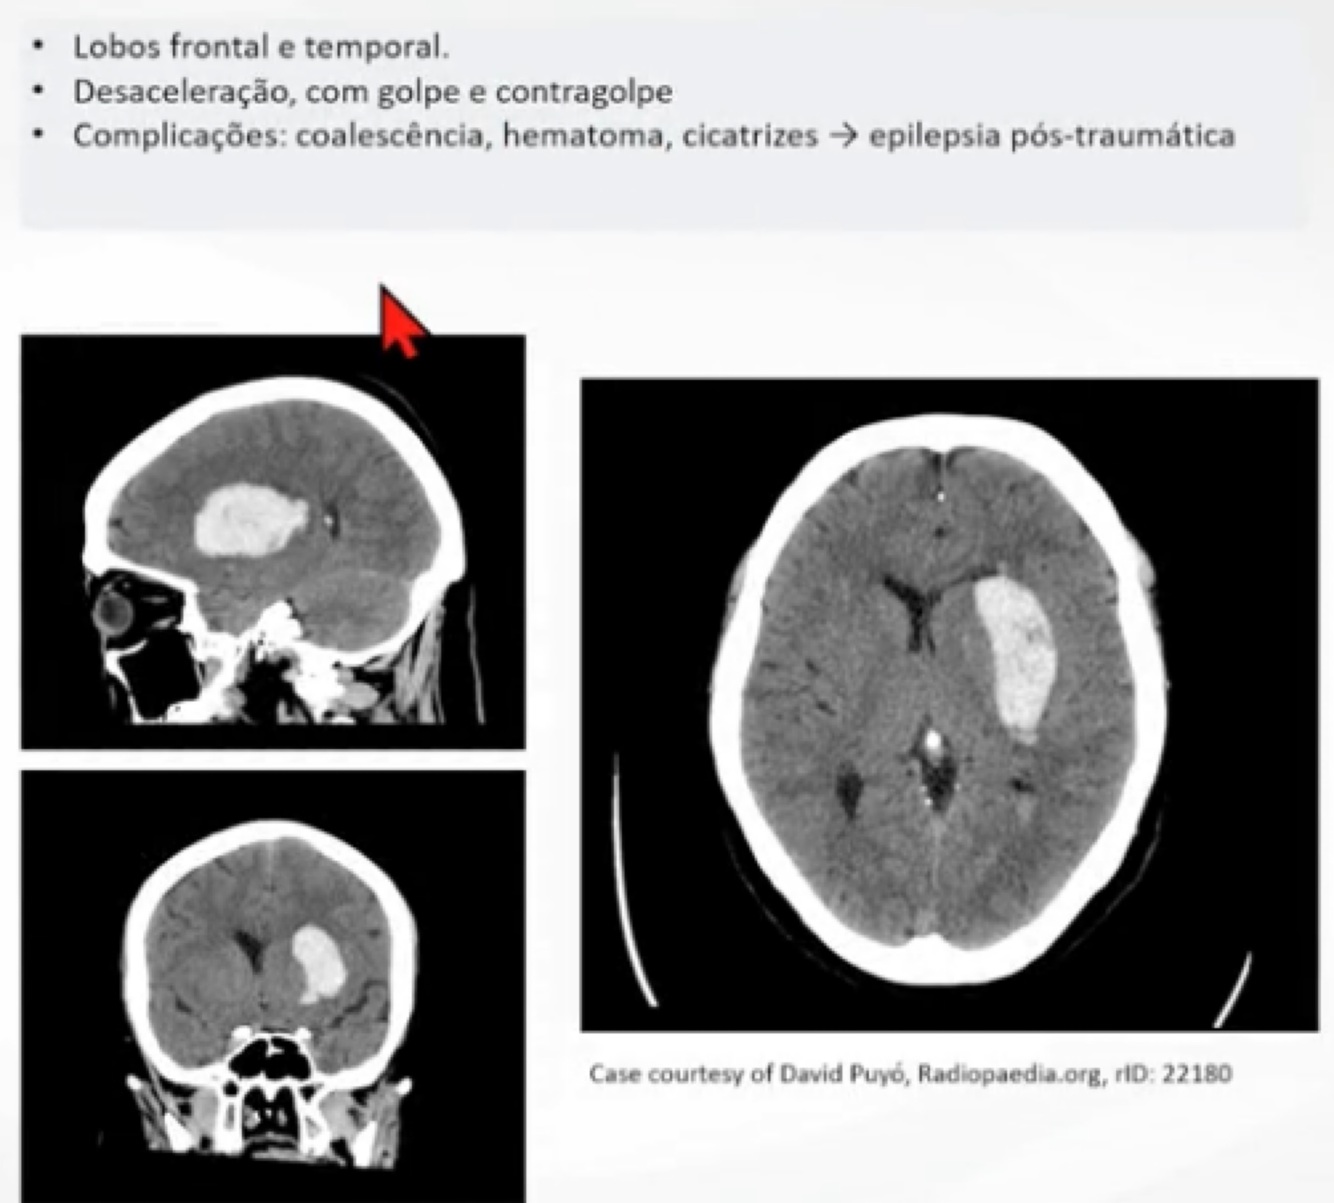

Q

Qual o Dx a seguir?

A

Lesão intraparenquimatosa.